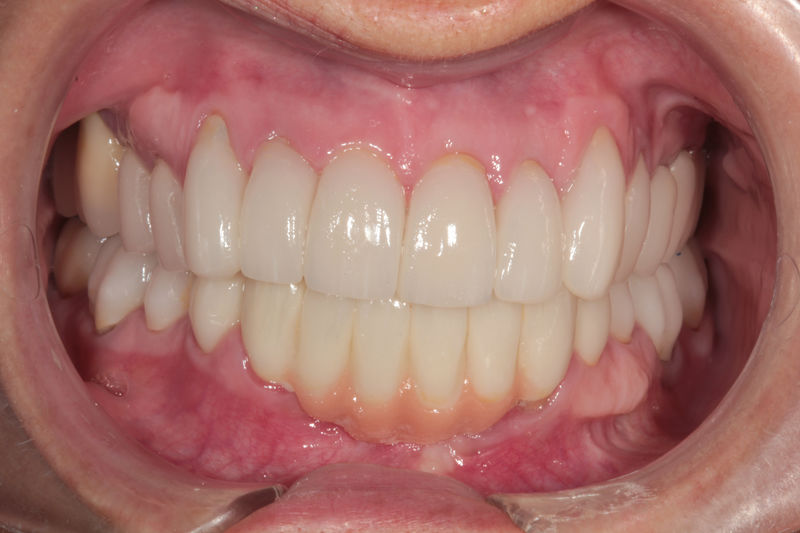

Amplia gama de tratamientos para mejorar la apariencia de la sonrisa, corrigiendo el color, la forma, el tamaño, la alineación y la posición de los dientes. Los procedimientos más comunes y solicitados incluyen el blanqueamiento dental, las carillas y coronas, así como las resinas.

Restauraciones fabricadas en el laboratorio con materiales estéticos, los cuales cubren de manera total dientes anteriores y posteriores. Se utilizan primariamente para restaurar dientes con caries, fracturas y/o defectos amplios, así como soportes de puentes. Para poder enviar el caso al laboratorio se toman impresiones utilizando materiales de impresión o técnicas modernas digitales.

Ortodoncia y coronas.